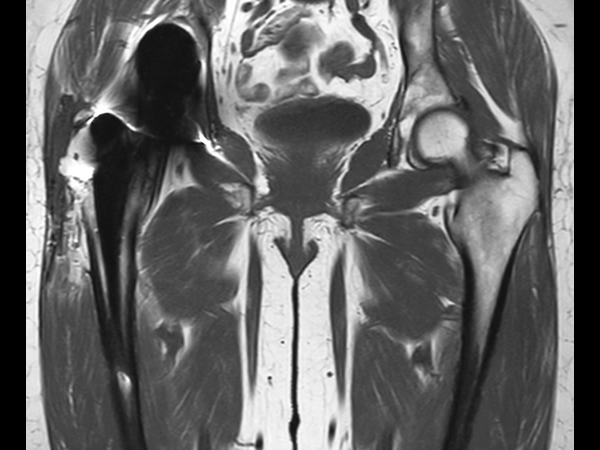

Hip imaging with metal implant

Used Solution

**Only for use with MR Safe or MR Conditional Implants by strictly following the Instructions for Use.